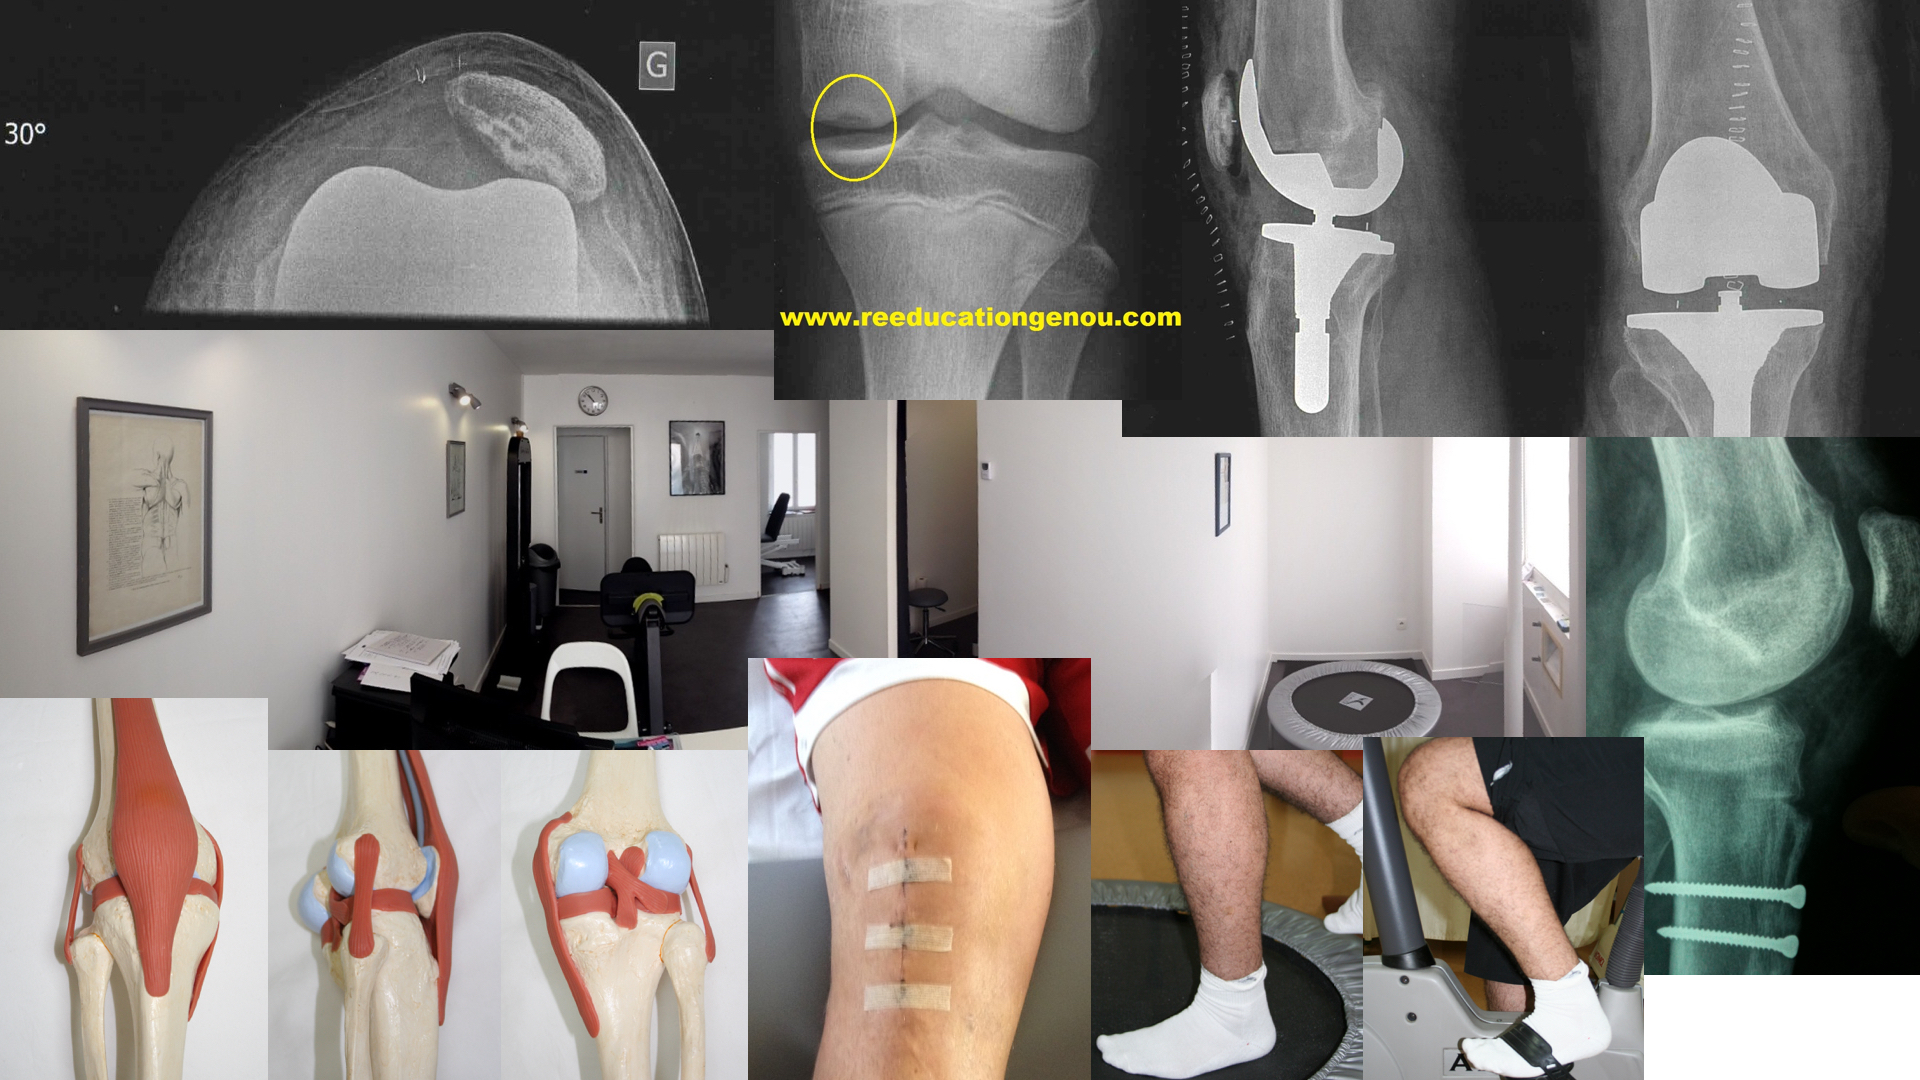

• les lésions des ligaments croisés donnent cliniquement des tiroirs lors du test de Lachman en flexion  30°

b) laximétrie : examen par le GNRB (société genouRob) ou télos radiologique

• la laxité est évaluée comparativement par un TELOS radiologique ou par le KT1000 manuel voire par le GNRB...cette machine est cependant l'avenir pour tester et différencier les ruptures partielles ou totales du LCA)